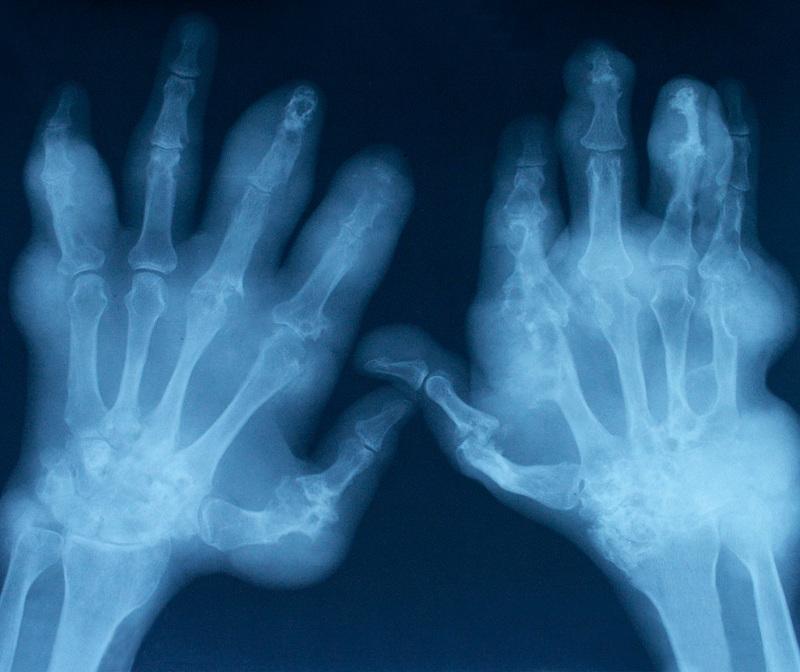

Ésta es una de las enfermedades reumáticas más frecuentes que existen, se produce por el desgaste del cartílago lo que ocasiona diversos problemas en el movimiento de las articulaciones. Es mucho más común en las mujeres que en los hombres y cada vez más personas jóvenes comienzan a padecerla, por eso resulta importante saber cómo prevenir la artrosis y cuidar nuestra salud. En unComo.com te damos algunas claves acerca de este tema.